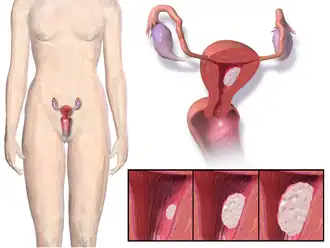

Das Endometriumkarzinom, auch Uterus- oder Korpuskarzinom (lat. Carcinoma corporis uteri), ist eine Krebserkrankung der Gebärmutterschleimhaut.

Aufgeschnittenes Uterus-Präparat mit dunkelroten, unregelmäßigen Verdickungen der Schleimhaut